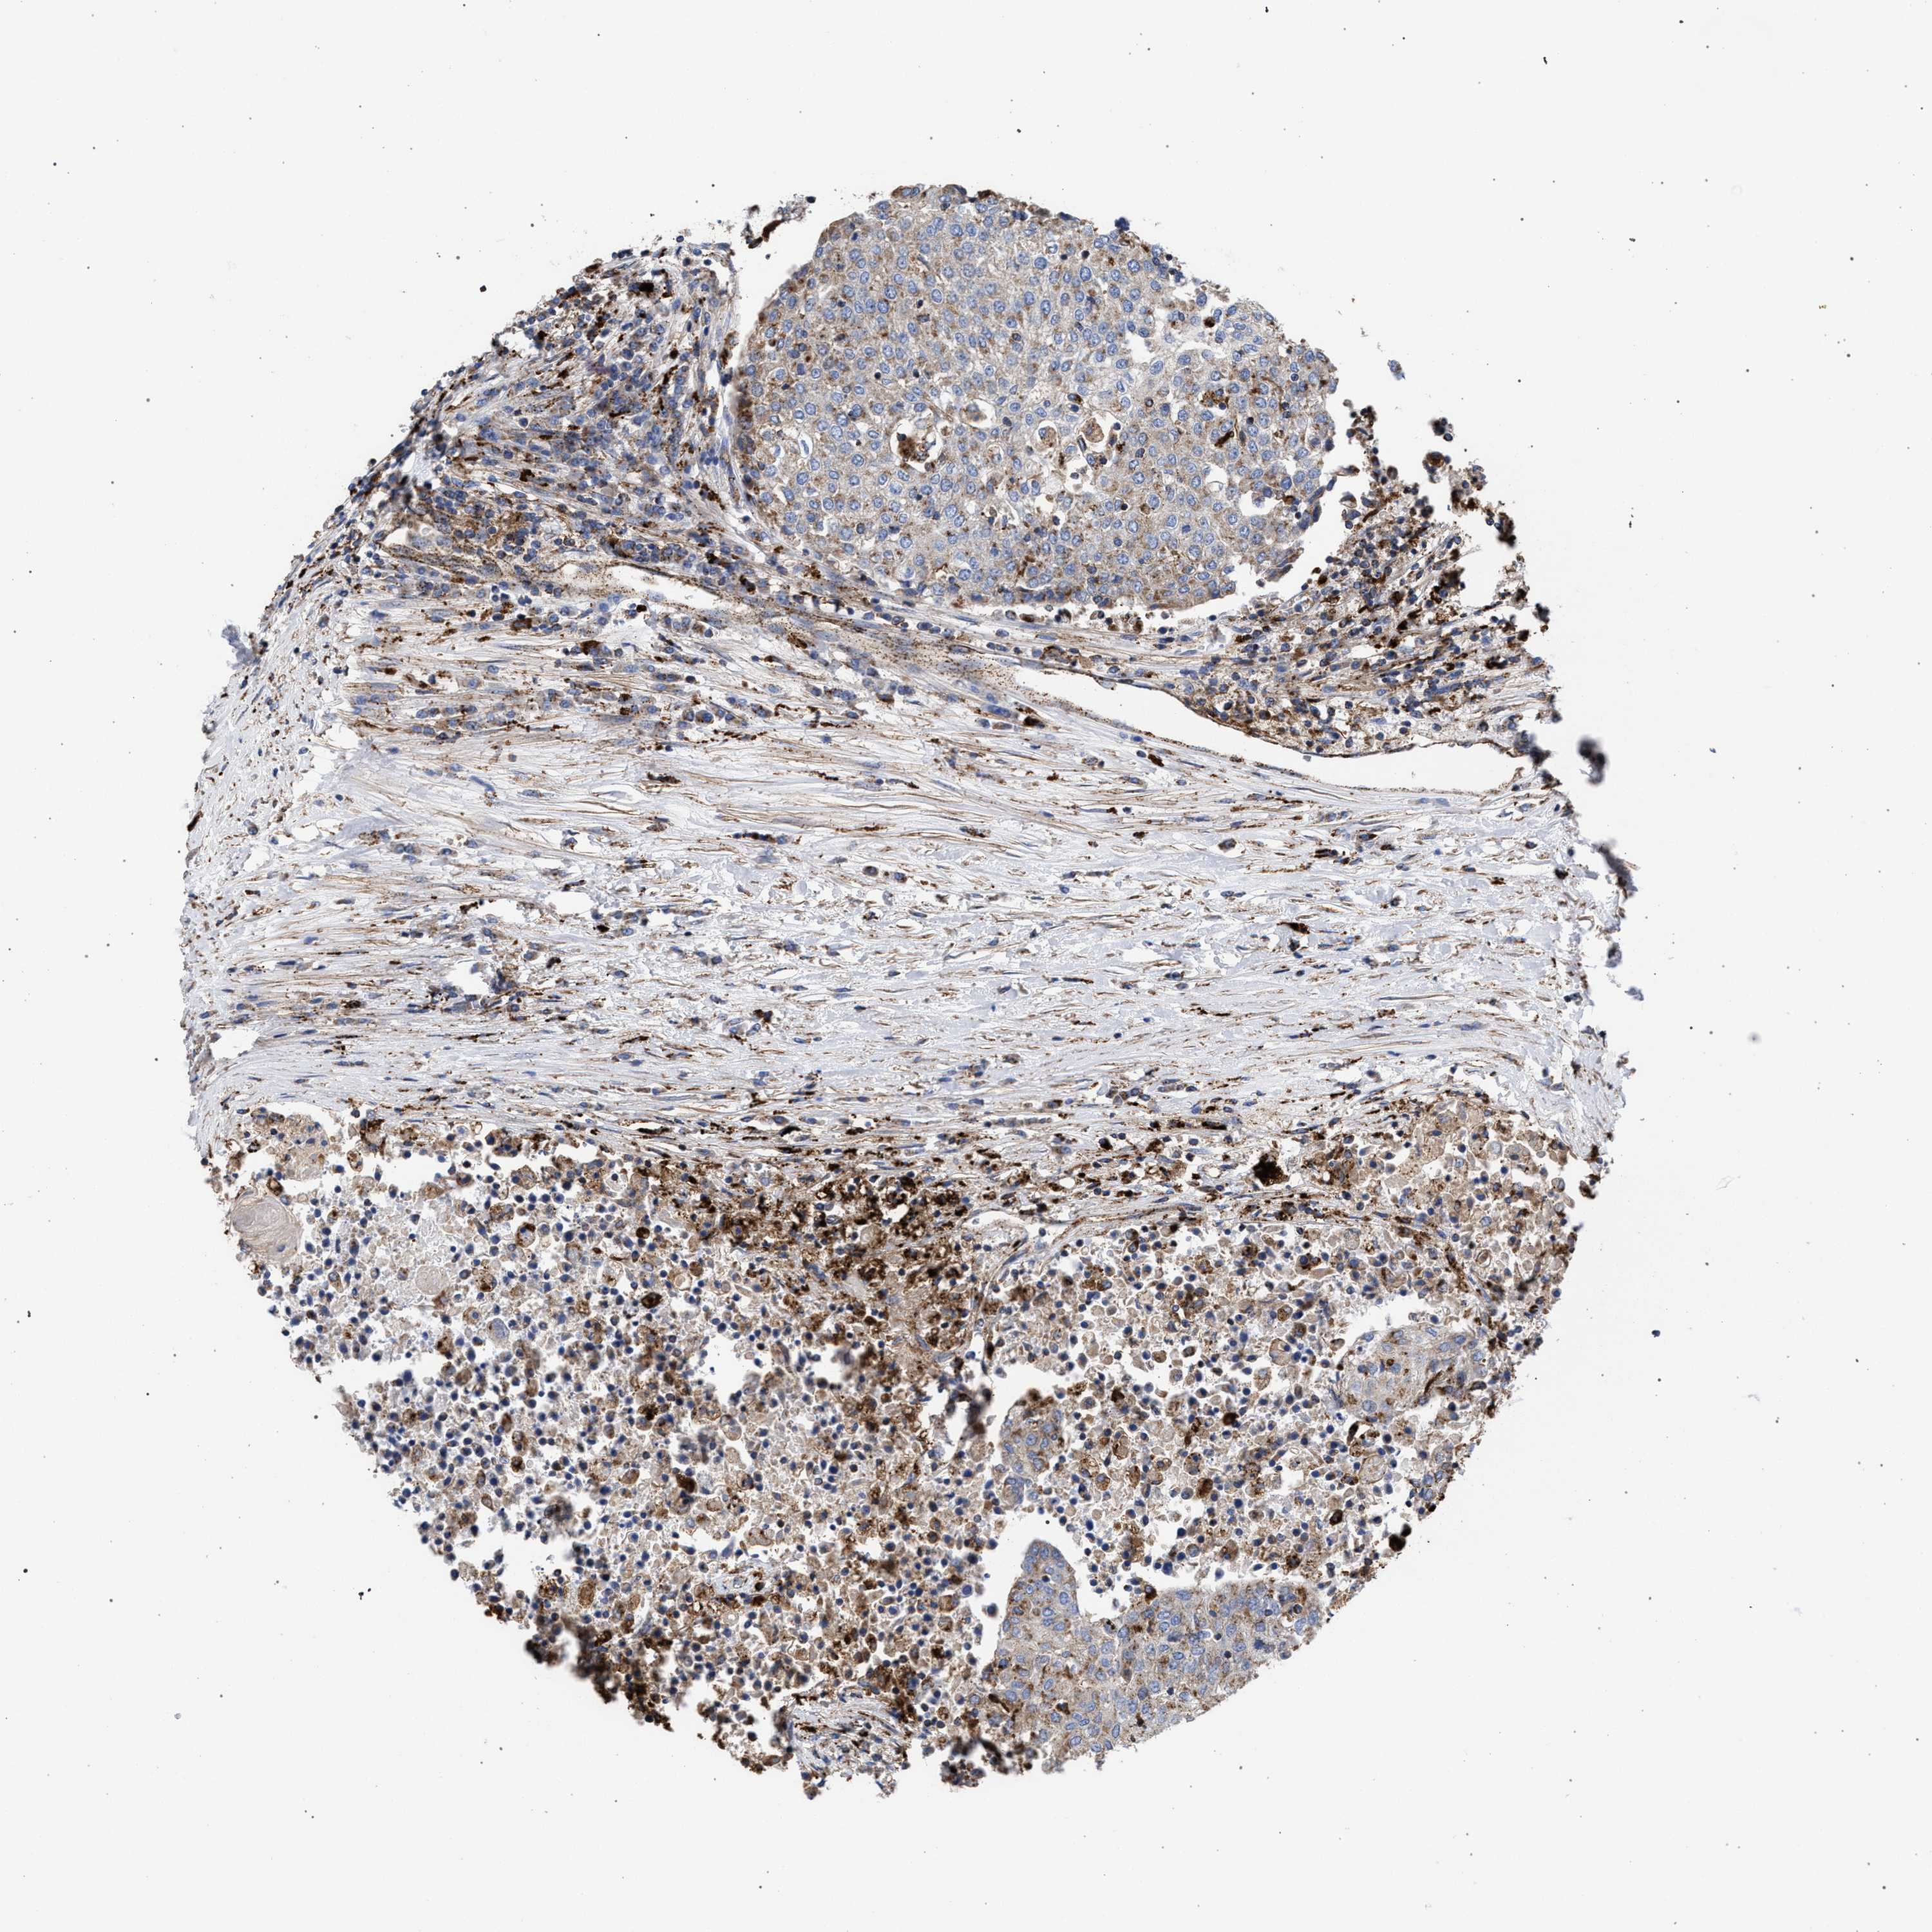

UROTHELIAL CANCER - Protein expressioni

A mouse-over function shows sample information and annotation data. Click on an image to view it in a full screen mode. Samples can be filtered based on level of antibody staining by selecting one or several of the following categories: high, medium, low and not detected. The assay and annotation is described here.

Antibody stainingi

Antibody staining in the annotated cell types in the current human tissue is reported as not detected, low, medium, or high, based on conventional immunohistochemistry profiling in selected tissues. This score is based on the combination of the staining intensity and fraction of stained cells.

Each image is clickable and will lead to virtual microscopy that enables deeper exploration of all samples and also displays staining intensity scores, fraction scores and subcellular localization as well as patient and tissue information for each sample.

Antibody HPA021546

Staining

High

Medium

Low

Not detected

Intensity

Strong

Moderate

Weak

Negative

Quantity

>75%

75%-25%

<25%

None

Location

Nuclear

Cytoplasmic/membranous

Cytoplasmic/membranous,nuclear

Urothelial carcinoma, High grade